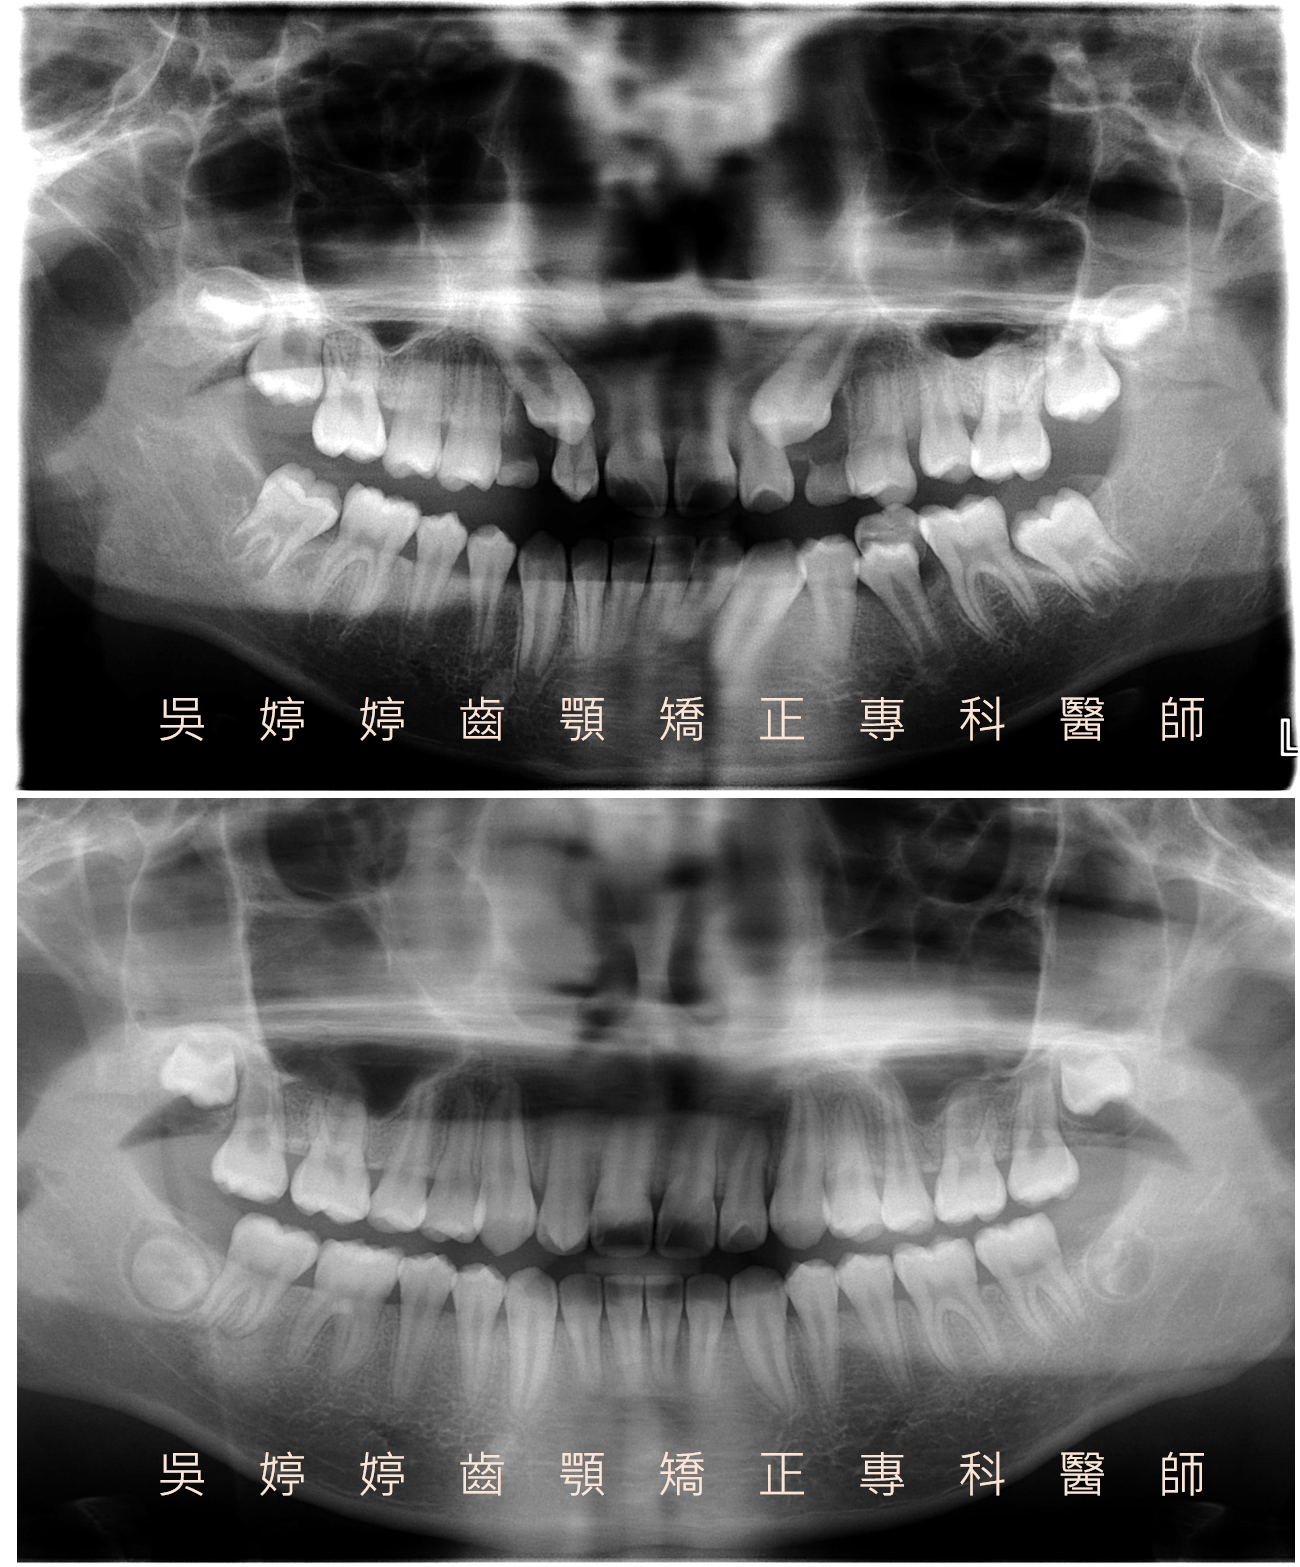

一位13歲女生於門診檢查發現,患有右上顎犬齒阻生齒、多生牙及咬合不正。

經過審慎檢查,發現阻生齒位在顎側,深度淺,除了牙胚位置異常之外,其上覆蓋著厚實的顎側軟組織也阻礙了萌發。因此計畫將阻生齒牙冠區域的軟組織移除。移除軟組織後即可見到牙冠,過程使用輕而持續之矯正力將阻生齒移到牙弓位置。另外拔除一顆多生牙及上下左右共四顆小臼齒以提供空間。治療完成後,達到良好穩定的咬合排列及自然和諧的外觀。